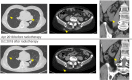

Case presentation: In 1999, a 56-year-old woman underwent left nephrectomy (clear cell carcinoma, pT1bN0M0). Seventeen years postoperatively, recurrence in the left lung hilum was observed. Despite administration of three molecular target drugs, all treatments were terminated due to adverse events. Nivolumab was initiated in December 2016. In August 2017, subcutaneous and lung metastases were observed. Moreover in January 2018, right renal metastasis was noted. After 22 cycles of nivolumab treatment, metastasis in the iliac bone was observed, and the patient was subjected to conventional palliative external beam radiation therapy. Five months after radiotherapy, there was significant reduction in multiple metastases. Here, we reported the case presenting with possible abscopal effect.